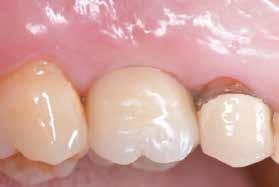

értünk el (19. ábra). Az okkluzális nyílást tefloncsíkkal és kompozittal zártuk (20. ábra). Mindezek után, posztoperatív kontroll röntgenfelvétel készült, amely a pótlás megfelelő illeszkedését mutatta (21. ábra). A hat hónapos utánkövetés során jól megfigyelhető a teltebb lágyszöveti profil és a megtartott kresztális csontszint (22–24. ábra)

és 20. ábra: Kompozittal zárt okkluzális nyílás. 21. ábra: Röntgenfelvétel a végleges korona felhelyezése után.

20 21 22 23 24

22. ábra: A hat hónapos utánkövetés: kiváló emergenciaprofil. — 23. ábra: A hat hónapos utánkövetés: a lágyszövetek jelentősen megvastagodtak. — 24. ábra: Hat hónapos utánkövetési röntgenfelvétel; a kresztális csontállomány megtartott.